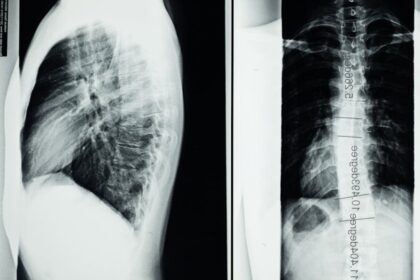

Un vétérinaire procédera généralement à un examen clinique complet, pouvant inclure une fibroscopie pour évaluer l’état des voies respiratoires. Il est important de documenter tout changement observé dans le comportement, la respiration ou l’état général de votre cheval. Une intervention précoce est indispensable afin de traiter le problème avant qu’il ne s’aggrave.